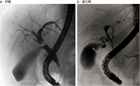

1. PSCとIgG4関連硬化性胆管炎との鑑別診断のためにERCPなどの直接胆管造影を行うことが推奨される(推奨度2、OJ)

1. PSCの診断のためにMRCPを行うことは強く推奨される(推奨度1、RSJG)